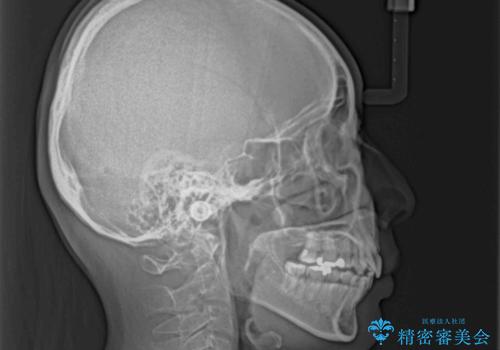

上顎前歯の突出を軽減 インビザラインによる抜歯矯正

- 上の前歯の突出感を気にして来院された患者様です。

目立たない装置を希望とのことで、上顎左右第一小臼歯を抜歯し、インビザラインにて矯正治療を行うこととしました。